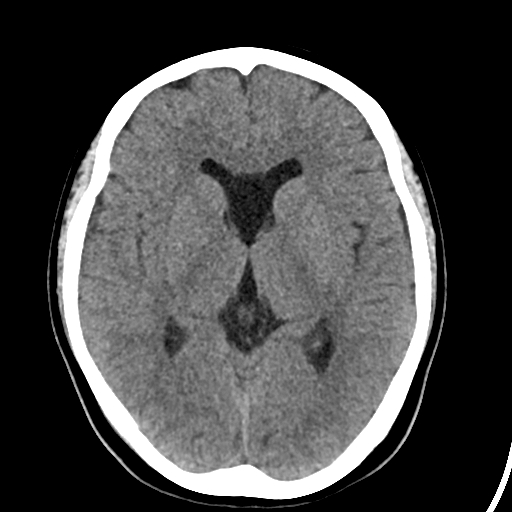

透明隔囊肿ct图片

透明隔间腔与透明隔囊肿鉴别及诊断标准